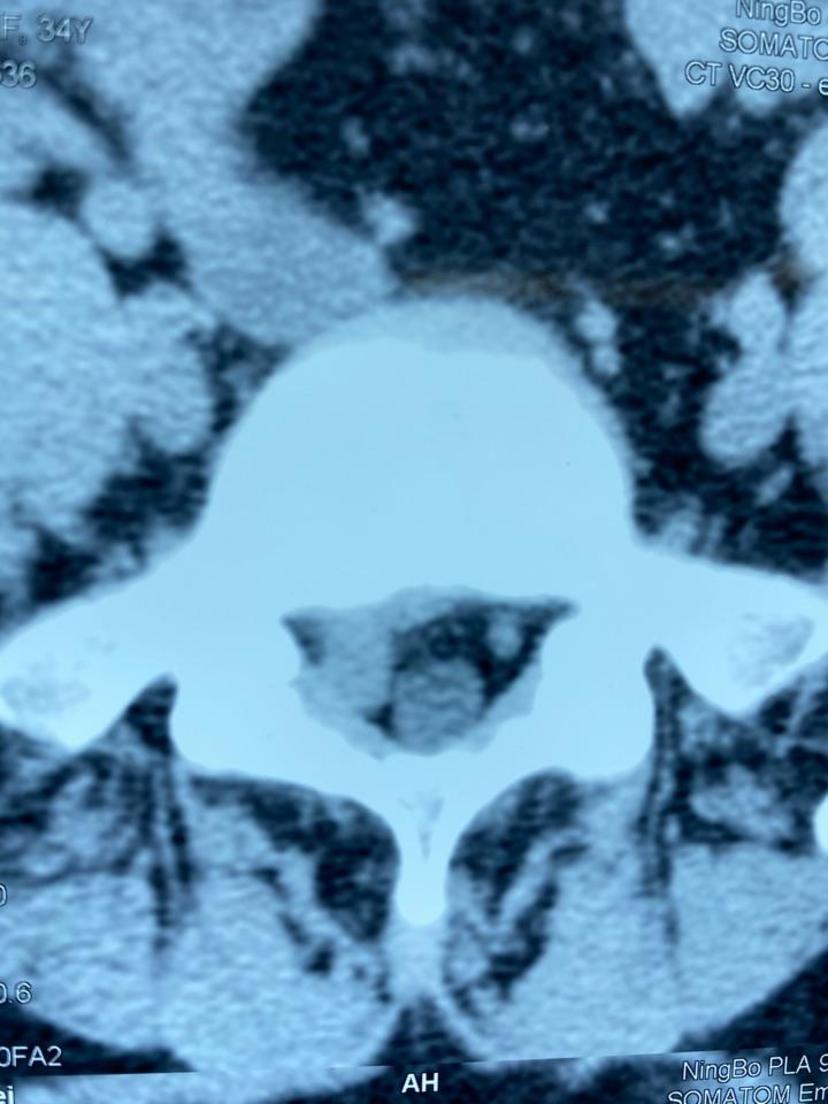

公司职员腰5-骶1椎间盘突出,右下肢疼痛麻木走不了路,利用假期三天时间(住院-手术-出院),完全恢复正常!